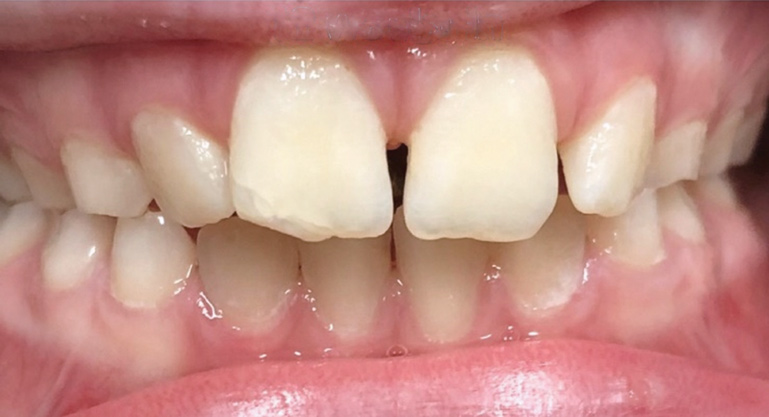

Fig 1. Functional shift in centric occlusion.

Figure 1

Fig 2. Functional shift in centric relation.

Figure 2

A common developmental abnormality is a localized anterior crossbite on permanent incisors, which may lead to trauma to these teeth. The most common cause of localized incisor crossbite is an anterior occlusal interference, which causes a functional shift when the patient moves from centric relation to centric occlusion (Figure 1 and Figure 2). This is not a true class III malocclusion, and proper diagnosis is critical to select the correct treatment. Sometimes this bite relationship is called a pseudo-class III relationship.2 Intervention in these cases is important because these teeth are at higher risk for recession, periodontal damage, and incisal chipping. Limited anterior braces and sometimes a palatal expander may be used to place the maxillary incisors facial to the mandibular incisors; this is referred to as "jumping the bite."